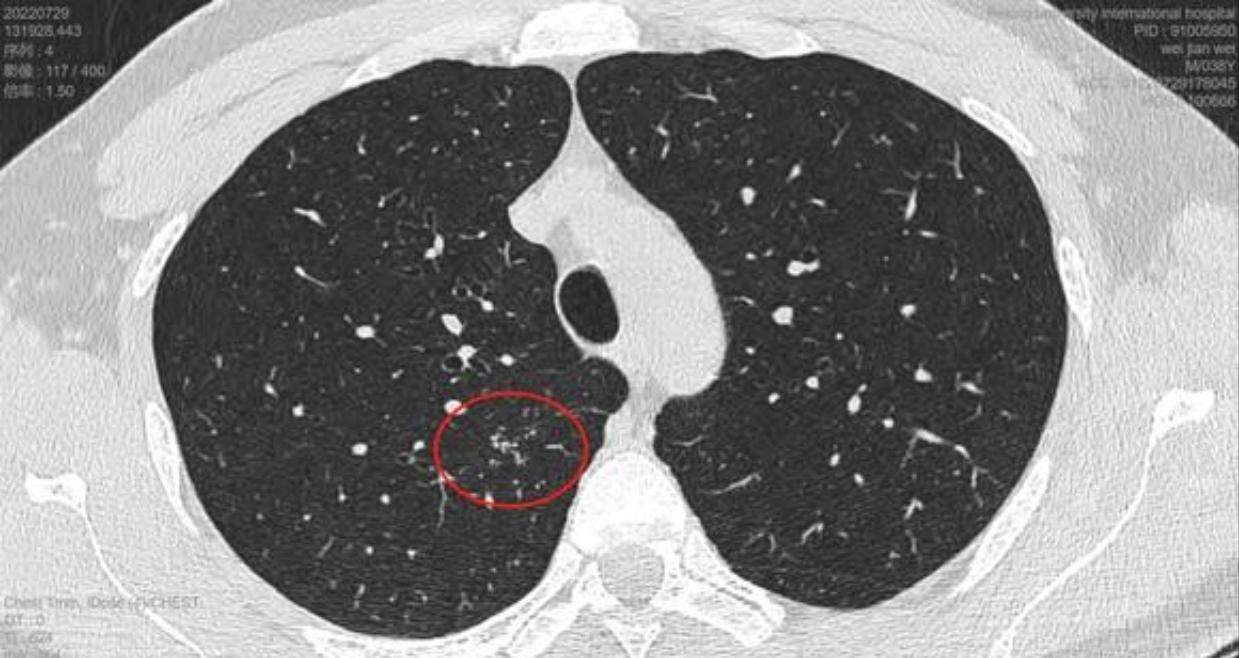

这是11月15日的CT图像与上次(7月29日)CT图像对比图:

再发一张:

辛苦主任,您看一下,结节虽然缩小了,还有1.7*0.9 CM,其他俩肺叶还有陈旧性病灶,应该继续服用拜复乐和夏枯草吗?8月份查过:男性肿标9项、过敏源检测(总IgE)、鳞状上皮细胞癌相关抗原、GM试验、隐球菌抗原、1,3-β-D葡聚糖 都是阴性,在正常范围内。就是结核感染T细胞还没查,您看是否需要查一下?主任辛苦您了,谢谢您!

敬爱的戴主任,有个好消息跟您汇报,我老公的肺结节听您的建议服用拜复乐和夏枯草后缩小啦,7月29日的CT报告是1.9*1.1cm,同一家医院11月15日的CT报告是1.7*0.9cm,颜色也变浅了,您真是火眼金睛,华佗在世,我们的保护神!我们全家人的恩人!真心地谢谢您!